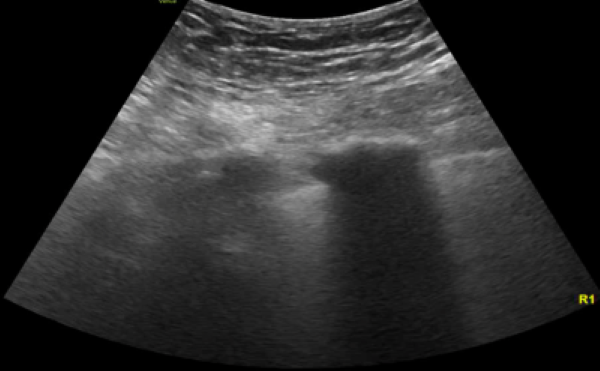

Image 1. Lung ultrasound shows diffuse B lines.

Ultrasound offers the benefit of earlier recognition of possible causes of respiratory failure. Lung ultrasonography is initially utilized to help identify the presence of lung and pleural abnormalities. For instance, the distribution of B lines are generally nonuniform in ARDS compared to diffuse pattern in cardiogenic pulmonary edema but is not definitive to distinguish them from one another.